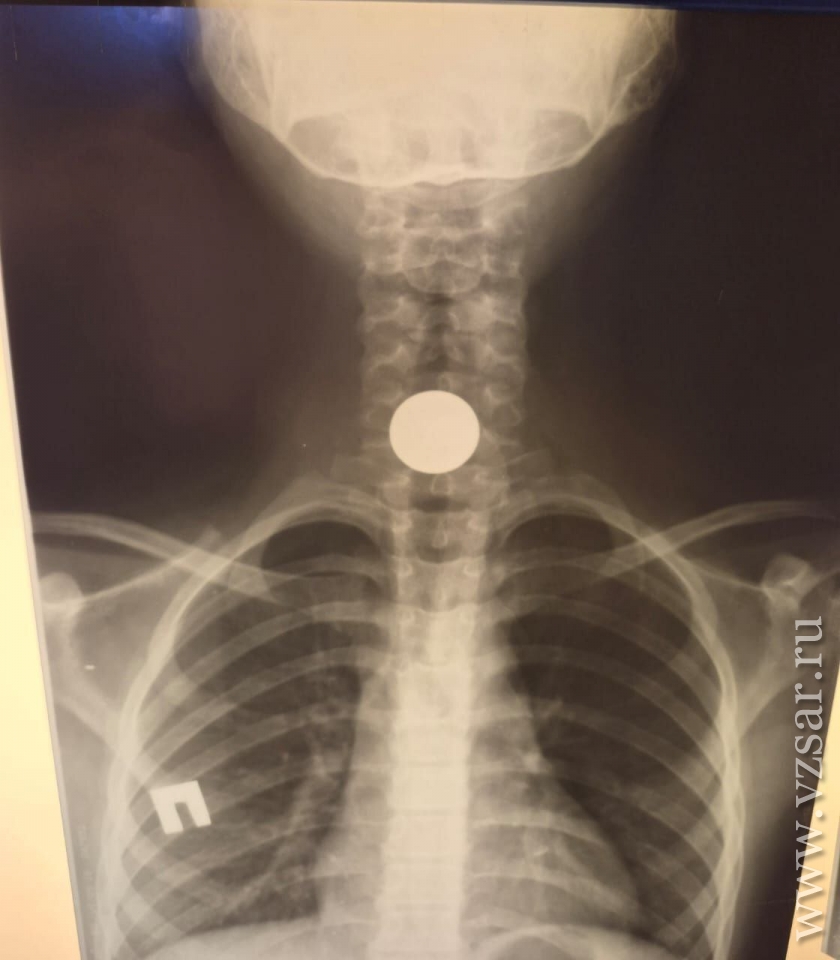

Вчера ночью в Балакове Саратовской области эндоскописты местной городской больницы извлекли из пищевода ребенка металлическое инородное тело.

Как сообщает тг-канал медучреждения, вечером в стационар БГКБ поступила 9-летняя девочка. Маленькая пациентка пояснила, что играла с друзьями во дворе в новых микрорайонах. При себе у нее была металлическая монетка достоинством 5 рублей, которую она спрятала под язык и случайно проглотила.

По дежурству из дома была приглашена заведующая эндоскопическим отделением Элла Бобрышева. Благодаря ей за считанные минуты под общим наркозом (детский возраст не позволяет иного проведения манипуляций при операциях) монетка была эндоскопически извлечена из пищевода ребенка.

"Очень хорошо, что сразу обратились, монета застряла на входе в пищевод. В таких случаях медлить нельзя, последствия могут быть необратимы", - отметила специалист, добавив, что в минувшие выходные другому пациенту (3-летнему мальчику) также извлекала две монетки достоинством 2 рубля каждая.

"Они чуть поменьше, но попадание такого предмета в желудочно-кишечный тракт все равно опасно. При поступлении ребенок, согласно рентгену, был с пищей в желудке, поэтому удаляли на следующий день, натощак", - рассказала врач.